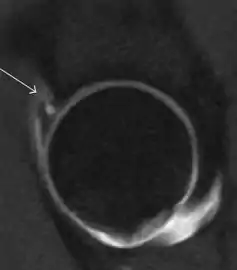

Synovial chondromatosis can be confidently diagnosed by X-ray when calcified cartilaginous chondromas are seen. However, other synovial proliferative processes, such as pigmented villonodular synovitis, require MRI for accurate diagnosis, although noncalcified synovitis can be suspected in radiographs by indirect signs, such as soft tissue swelling and/or erosions in the femoral head, femoral neck, or acetabulum (Figure 7).[1]

Figure 7:

Axial CT image of pigmented villonodular synovitis eroding the posterior cortex of the femoral neck.[1]

Sagittal T2* gradient echo image showing a posterior soft tissue mass with hypointense areas secondary to hemosiderin deposition.[1]

X-ray of synovial chondromatosis.[1]

CT of synovial chondromatosis.[1]

In synovial proliferative disorders, MRI demonstrates synovial hypertrophy. In the case of PVNS, characteristic foci of low signal intensity related to hemosiderin deposition are better seen on gradient echo T2* images (Figure 7). In the case of synovial osteochondromatosis, the synovial hypertrophy is accompanied by intermediate signal cartilaginous loose bodies and/or low signal calcified loose bodies.[1]